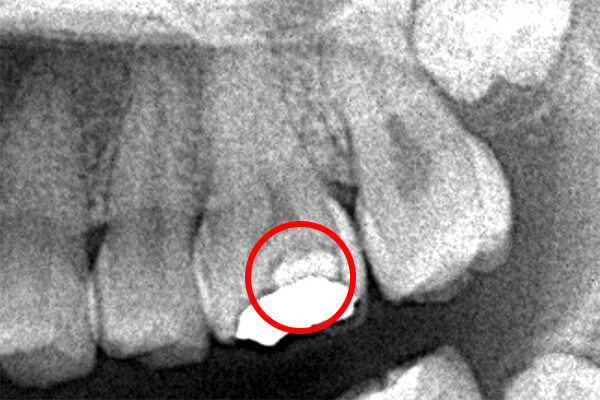

それは歯の先に枝分かれが多く存在し、そこにばい菌が入り込んで難治性となっているからです。ではその場合どうするのか?外科治療をします。その枝分かれの部分を切り落とすのです。今回はその前後のレントゲンの写真をお見せします。

| 根の中にお薬を充填した後のCT画像。やはり根の先に黒い影があるのがわかります。 |

| 根の先の黒い影は消失しました。 | 術後6ヶ月のCT画像です。こちらでも、根の先に黒い影は見当たらないです。 |